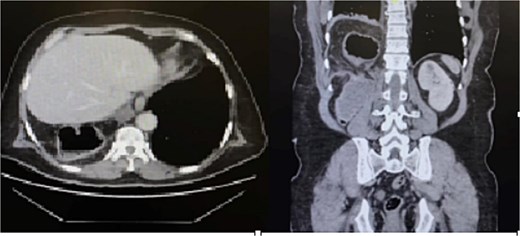

The patient was initially resuscitated with intravenous fluids. An urgent abdominal computed tomography (CT) scan was performed, revealing a herniated and obstructed segment of large bowel loops with mesenteric fat at the hepatic flexure, likely through the posterior right hemidiaphragm (Fig. 1). The scan showed a proximally dilated cecum and ascending colon, with a transitional zone observed at the neck of the hernia, leading to a distally collapsed colon. Additionally, there was an area suspicious for pneumatosis intestinalis within the obstructed bowel segment, along with adjacent fat stranding and free fluid—findings that raised concerns for strangulation or early ischemia. The scan also indicated a right-sided pleural effusion and adjacent atelectasis (Fig. 2).

CT scan of the abdomen revealed a herniated obstructed segment of large bowel loops and mesenteric fat at the hepatic flexure, likely through the posterior right hemidiaphragm.